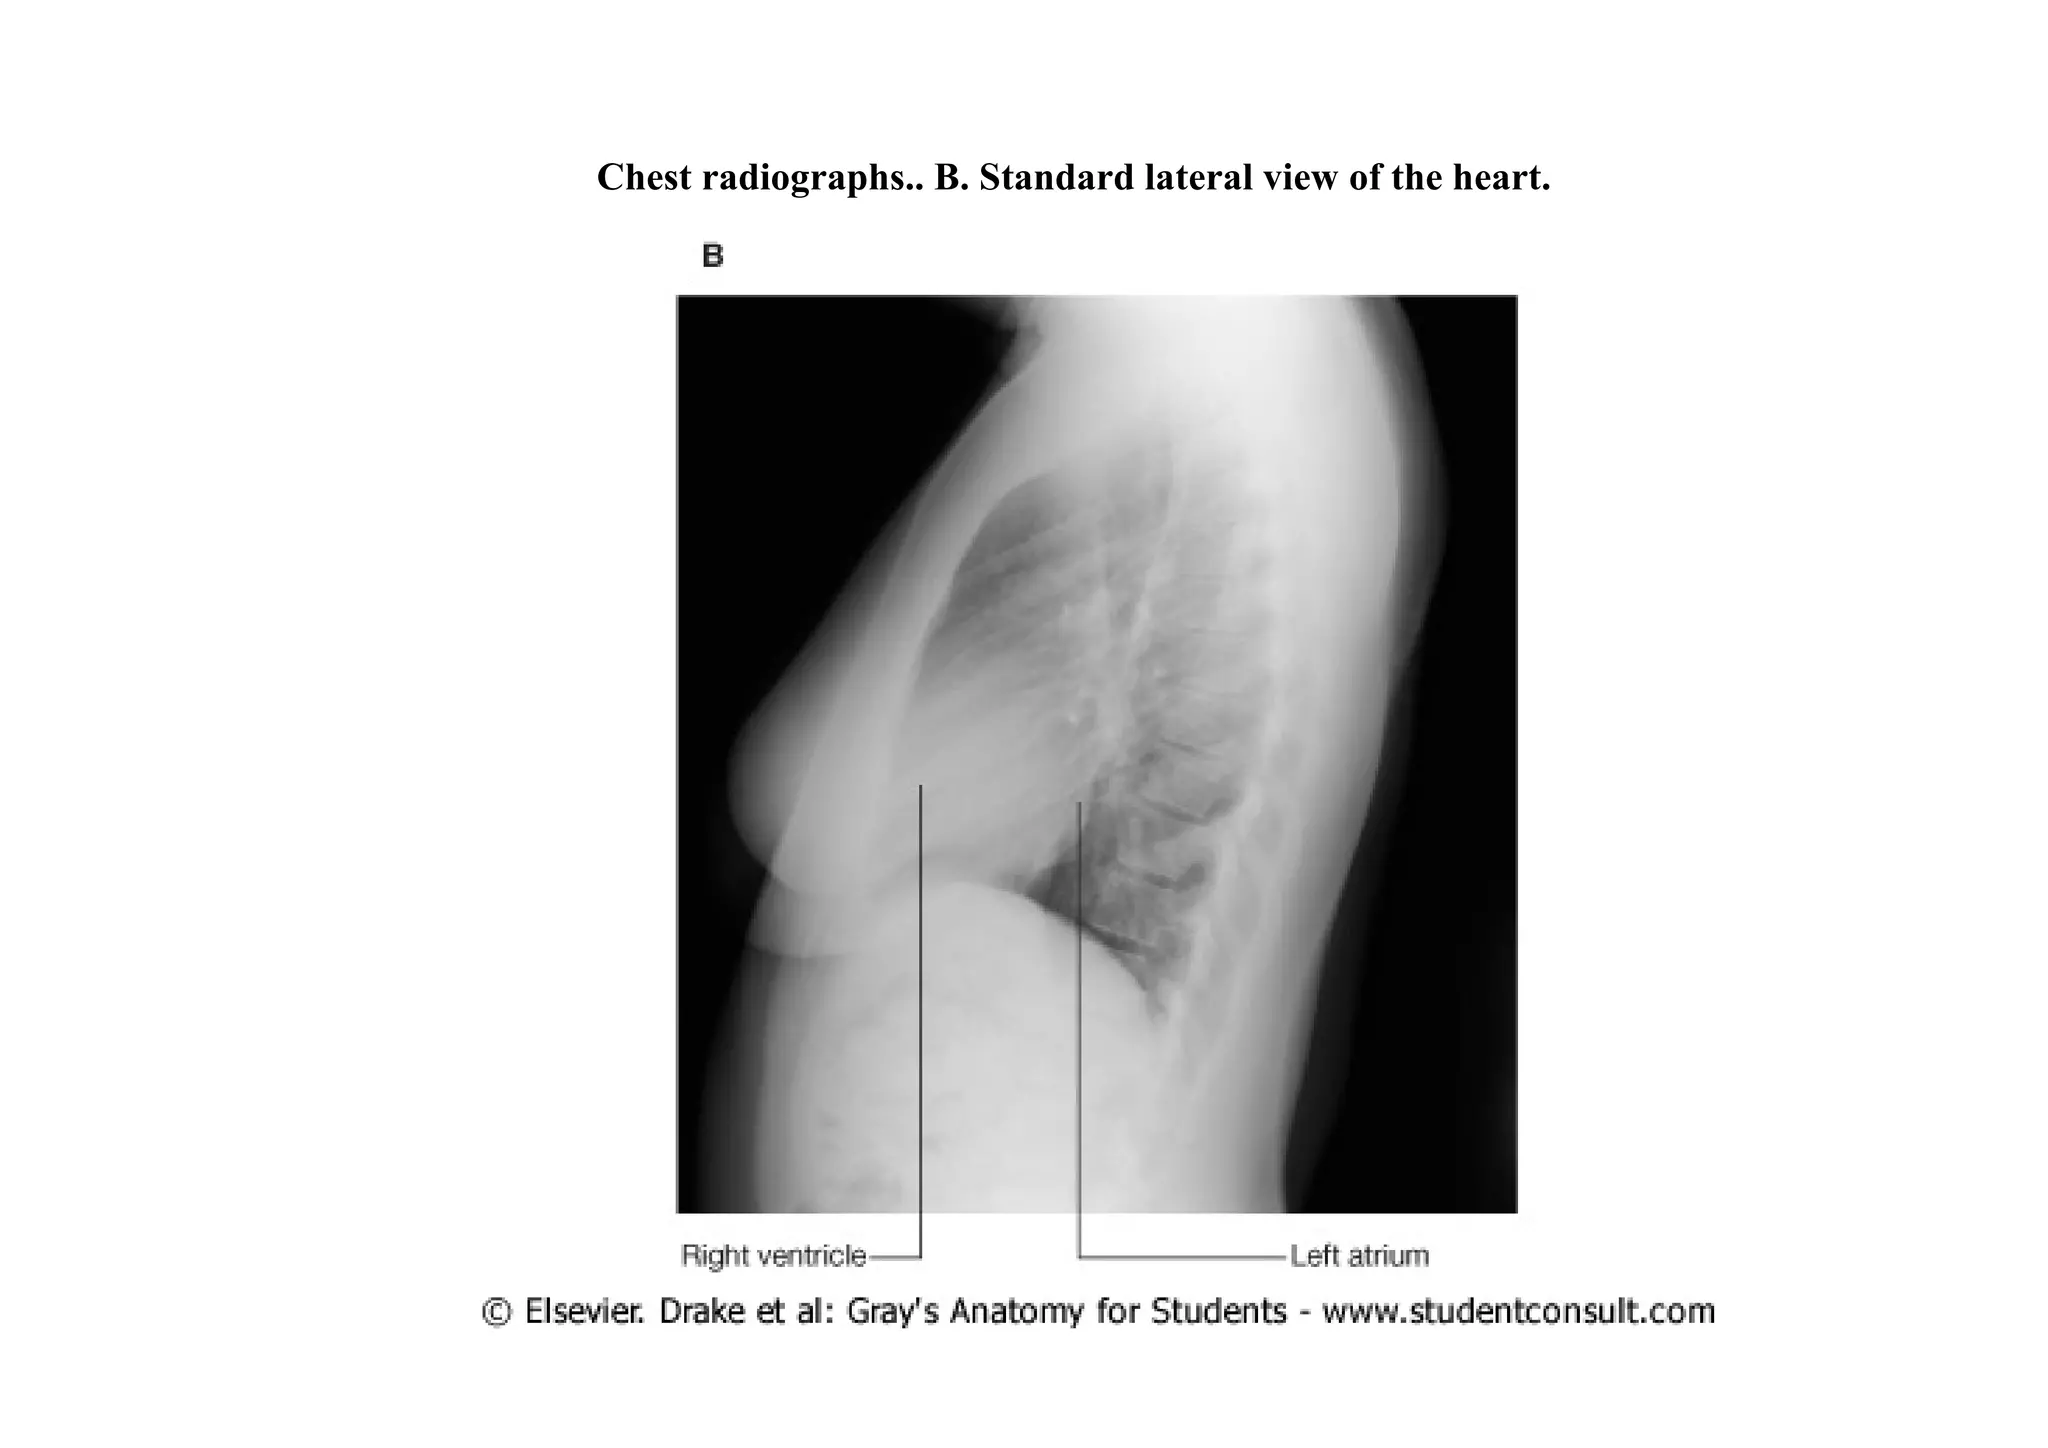

Radiological examination of the heart

•   For radiologic evaluations, a thorough understanding of the structures defining the cardiac

borders is critical. The right border in a standard posterior-anterior view consists of the

superior vena cava, the right atrium, and the inferior vena cava. The left border in a similar

view consists of the arch of the aorta, the pulmonary artery, and the left ventricle. The inferior

border in this radiologic study consists of the right ventricle and the left ventricle at the apex.

In lateral views, the right ventricle is seen anteriorly, and the left atrium is visualized

posteriorly

Chest

radiographs.

A. Standard

posterior-

anterior view

of the chest..